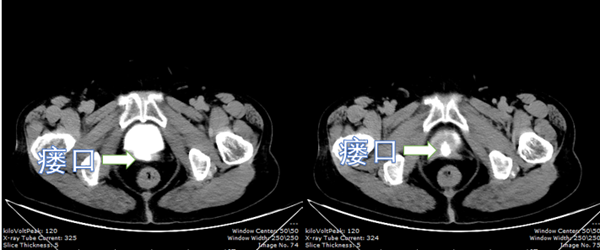

牵牛要牵牛鼻子,治瘘找到瘘孔是关键。由泌尿外科蒋欣杰副主任医师,许强主治医师运用内窥镜反复探寻,终于在膀胱内偏右侧近尿道端找到瘘孔。因为阴道及开腹都做过手术,哪种手术方式均有难度。随后,在顿主任,蒋欣杰副主任医师的讨论下决定进行开腹经膀胱手术。择日,由顿金庚教授带领许强,陈诚,朱昱宏三位年轻医师,进行开放手术。术中,经腹膜外显露膀胱,由于瘘口位置低又深极难显示,顿主任自主创“挑灯天使”法,即经阴道逆行插入气囊导尿管,提起气囊导尿管法,将该瘘口由暗处,深处,变浅变亮,逐层解刨,分层缝合,阴道壁,膀胱肌层,黏膜层,共计四层。术毕,关闭膀胱注入美蓝反复测试阴道内干净无美蓝渗出。真正做到了滴水不漏的承诺。